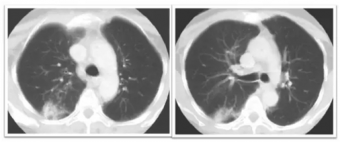

肺是放射敏感器官, 放射性肺炎 (Radiation Peumorutis RP)是指肺部一年內(nèi)接受過放射治療的患者,出現(xiàn)連續(xù)兩周以上的咳嗽、呼吸困難等肺部癥狀,同時肺部的影像學(xué)與照射野一致的片狀或條索狀陰影。RP是由炎性因子介...